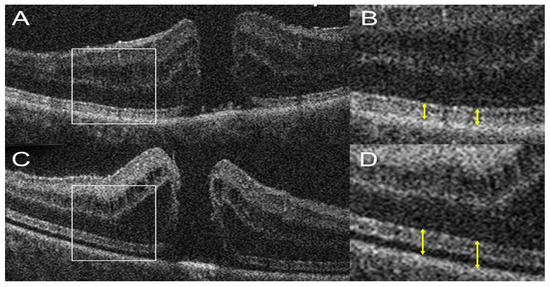

- Ehlers, J.P.; Ohr, M.P.; Kaiser, P.K.; Srivastava, S.K. Novel Microarchitectural Dynamics in Rhegmatogenous Retinal Detachments Identified with Intraoperative Optical Coherence Tomography. Retina 2013, 33, 1428–1434. [Google Scholar] [CrossRef]

- Abraham, J.R.; Srivastava, S.K.; K Le, T.; Sharma, S.; Rachitskaya, A.; Reese, J.L.; Ehlers, J.P. Intraoperative OCT-Assisted Retinal Detachment Repair in the DISCOVER Study: Impact and Outcomes. Ophthalmol. Retin. 2020, 4, 378–383. [Google Scholar] [CrossRef] [PubMed]

- Lee, L.B.; Srivastava, S.K. Intraoperative Spectral-Domain Optical Coherence Tomography during Complex Retinal Detachment Repair. Ophthalmic Surg. Lasers Imaging 2011, 42, e71–e74. [Google Scholar] [CrossRef]